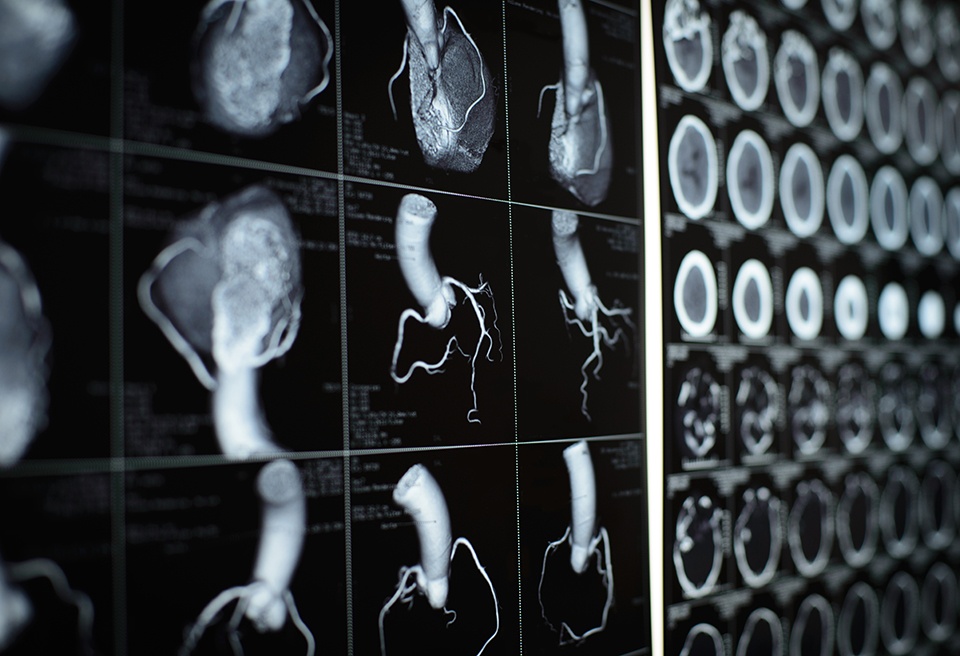

Artificial intelligence (AI) may be able to prevent unnecessary diagnostic testing in those with stable angina, ...